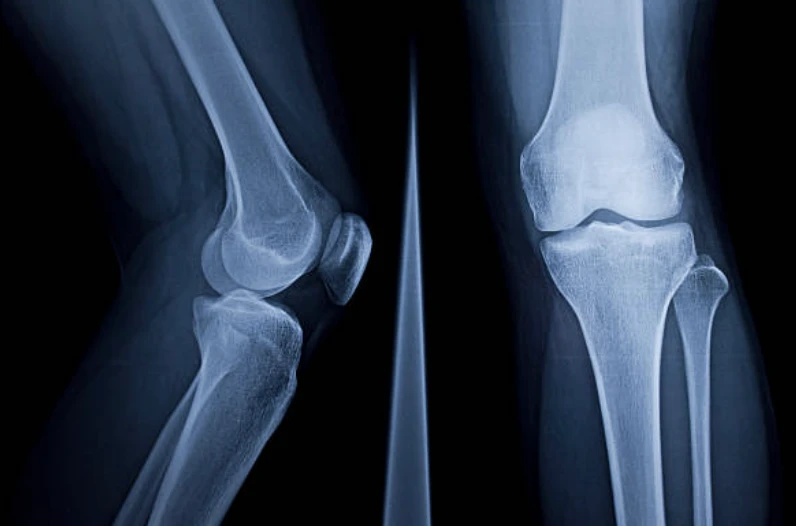

- 무릎 부상에 대해서 병원 진료를 받을 때는 일반적으로 X-레이, MRI, CT 스캔 또는 관절경과 같은 진단 절차가 진행될 수 있습니다.

무릎 통증에 대한 병원 진료

- 엑스레이(X-ray) : 눈에 보이지 않는 전자기 에너지 빔을 사용하여 내부 조직과 뼈 및 장기에 대한 사진을 필름에 만듭니다.

- CT 스캔 : X-ray 기술을 사용하여 신체의 수평 또는 축 이미지를 만들어 냅니다. CT 스캔은 뼈, 근육, 지방 및 장기를 포함한 신체의 모든 부분에 대해 상세히 이미지화합니다.